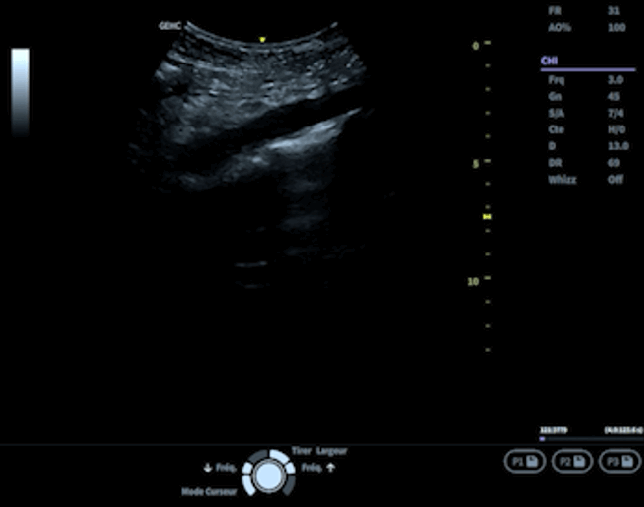

2. Réalisation des coupes échographiques

• Coupe longitudinale : Cette vue confirme la mesure transversale en offrant une évaluation complémentaire.

Les médecins doivent également être vigilants aux artéfacts échographiques (voir glossaire) susceptibles de compliquer l’interprétation, comme le cône d’ombre postérieur ou le renforcement postérieur.